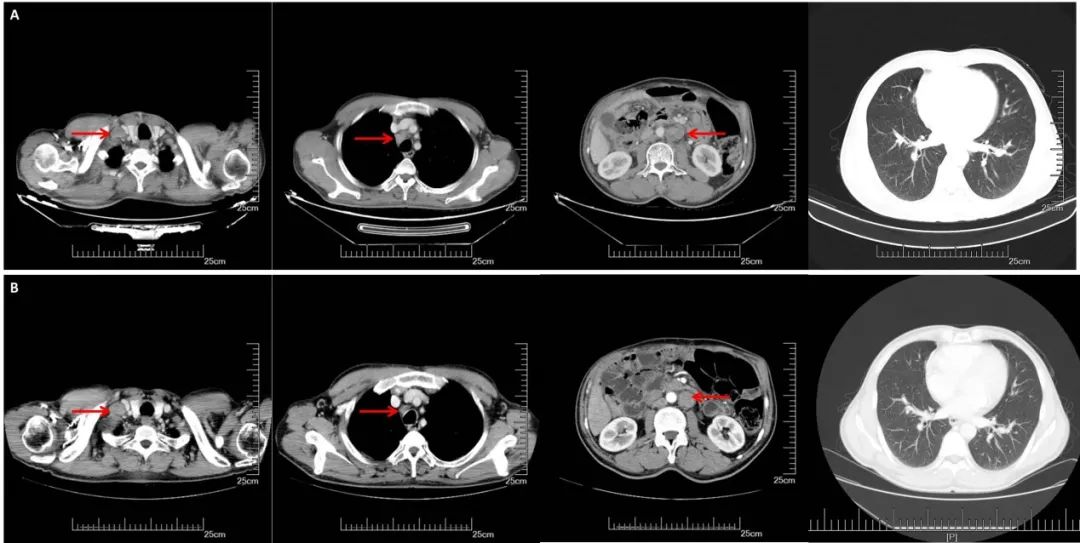

A:CT增强(2017.09.29):右锁骨上,纵膈,腹腔淋巴结明显增大,双肺无明显变化;B:CT增强(2018.03.27):腹膜后多发增大淋巴结较前缩小,右侧锁骨上纵隔内见多发淋巴结,部分较前增大,双肺较前变化不大。